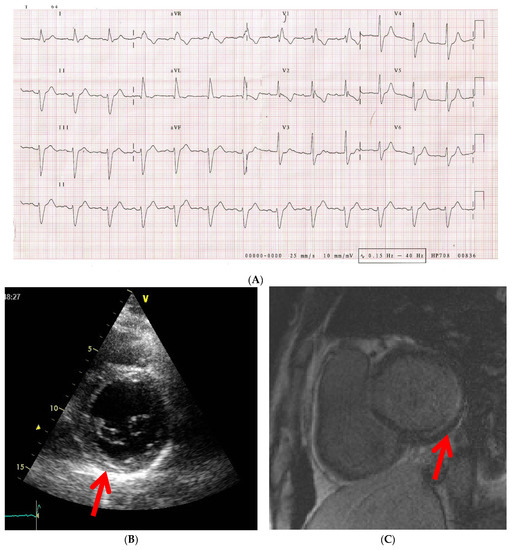

Overt cardiac disease is seen in 15–35% of cases, but in morpho-pathological studies it is identified in 21–100% of situations, and most patients suffer from subclinical disease [44,58] (Figure 3). Still, there are reasons to believe that the true prevalence is much higher, given the fact that signs and symptoms are occult, heart pathology tends to coexist with pulmonary, musculoskeletal and esophageal comorbidities, which can lead to false identification of symptoms and diagnostic tests have relative inaccuracy [10,11].

Figure 3.

42 years old male patient diagnosed with dcSSc, normal epicardic coronary arteries. (A) ECG tracing with trifascicular block (RBB, AFB, grade 1 AV block), (B) 2DTTE PSAX image at the base of the LV showing hyperechogenic area in the infero-basal segment of the LV (red arrow); (C) CMR image showing LGE in the infero-basal segment suggestive of subendocardial and mid-wall scar at this level (red arrow). dcSSc, diffuse cutaneous systemic sclerosis; RBB, right bundle branch block; AFB, anterior fascicular block; AV, atrio-ventricular; 2DTTE, two-dimensional transthoracic echocardiography; PSAX, parasternal short-axis view; LV, left ventricle; CMR, cardiac magnetic resonance; LGE, late gadolinium enhancement.